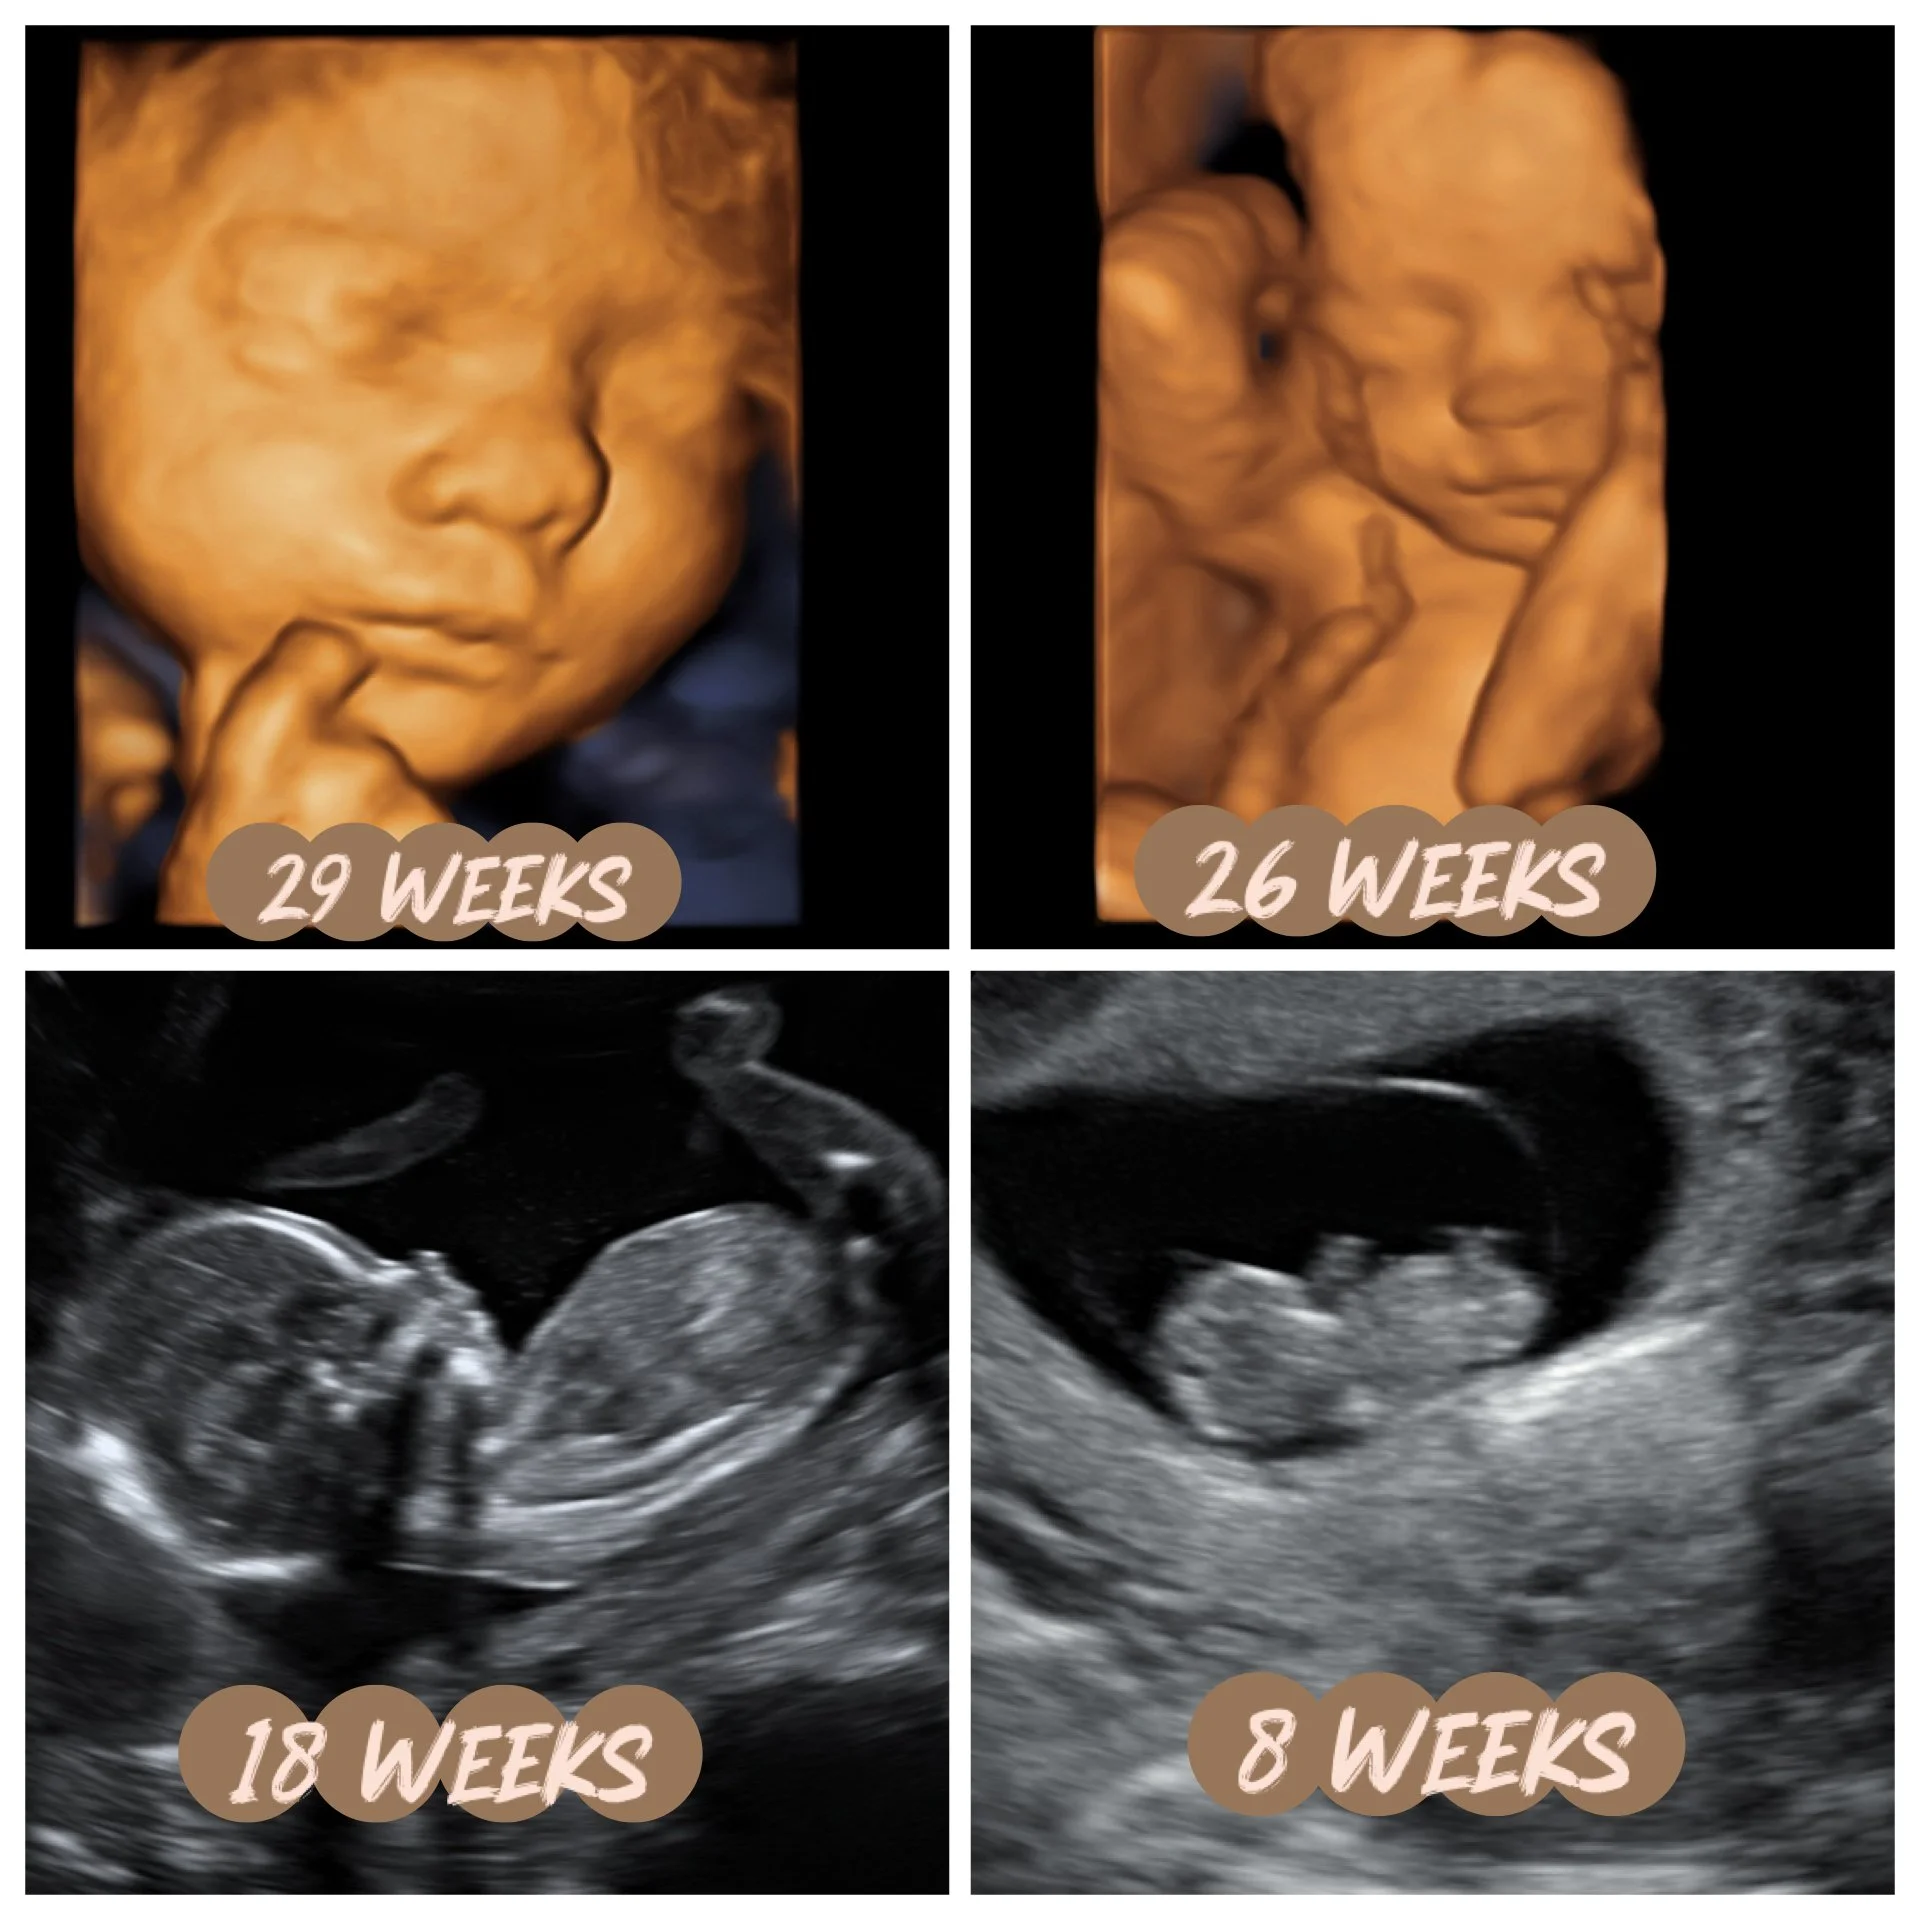

3D/4D/HD Images We Love

Here are some adorable images of babies we’ve taken here at First Glimpse. These images are taken from our customers, on our machine, here in Baton Rouge, LA. We understand that not everyone’s images will look like this, but the greater the amount of amniotic fluid in utero, the better the chance is that we will have wonderful images. Things still play into other factors that are out of our control, such as, placenta location, body habitus and baby’s position. Sometimes we have to step back and realize these babies are in small confined spaces & can only move so much. So we need to be thankful for what images they do give us. The parents who come into these scans with the most open & accepting minds typically get the best images. We give what energy we get, sometimes; the most positive the better!

Now enjoy some of our cuties!